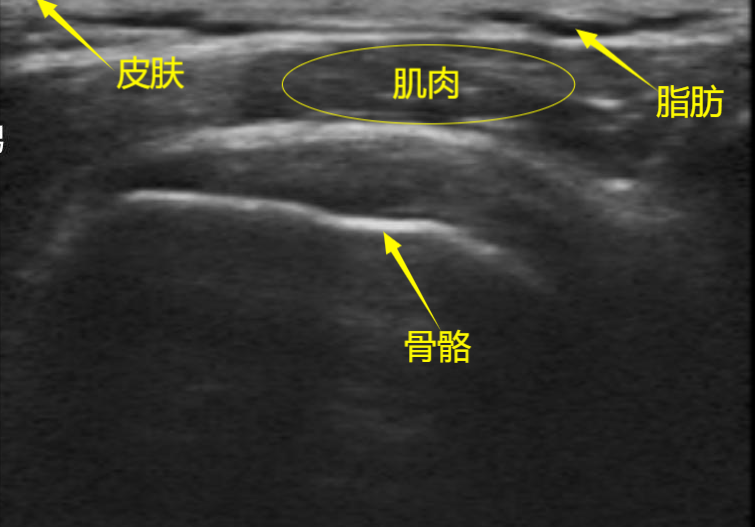

In sonograms, various echo imaging patterns are primarily caused by differences in acoustic impedance. As shown in the figure above, due to the high acoustic impedance of bones, they appear as high echoes on the image. The general order of acoustic impedance values is: Air <Fat <Water <Blood <Kidney <Liver <Muscle <Skin <Bone